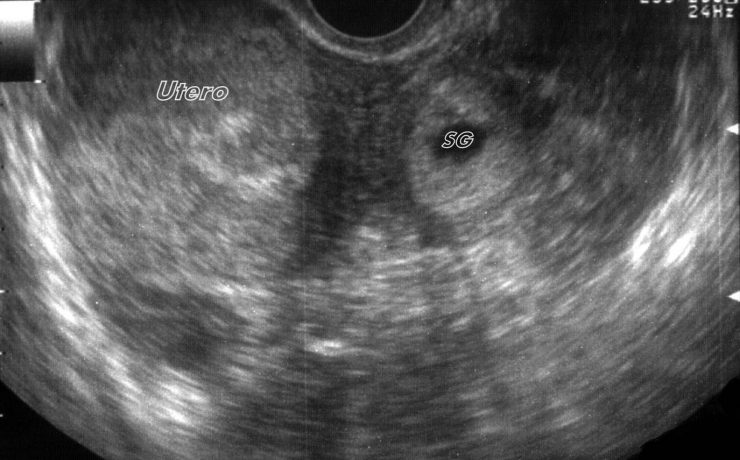

Durante el embarazo y la lactancia, la mama puede verse afectada por una variedad de trastornos únicos y específico, incluyendo trastornos benignos, relacionados con los cambios fisiológicos, inflamatorios, enfermedades infecciosas, papilomatosis juvenil y tumores benignos y malignos. Pacientes con carcinoma de mama asociada al embarazo presentan diagnóstico de neoplasias avanzadas y